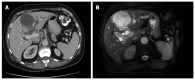

Cystic hepatic neoplasms are rare tumors, and are classified into two separate entities: mucinous cystic neoplasms (MCNs) and intraductal papillary mucinous neoplasms of the bile duct (IPMN-B). We report the case of a 56-year-old woman who presented with abdominal pain and jaundice due to the presence of a large hepatic multilocular cystic tumor associated with an intraductal tumor. Partial hepatectomy with resection of extrahepatic bile ducts demonstrated an intrahepatic MCN and an intraductal IPMN-B. This is the first report of the simultaneous occurrence of these two histologically distinct entities in the liver.